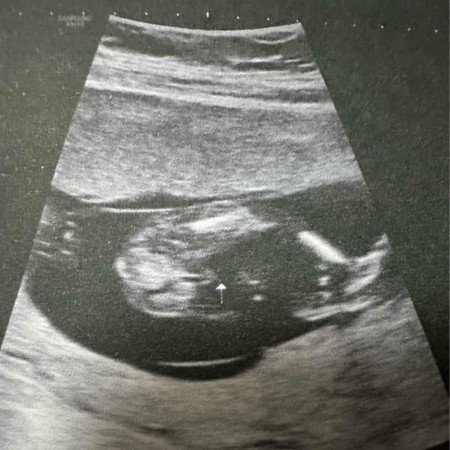

แม่ๆ ช่วยดูหน่อยค่ะ น้องเป็น ชาย หรือหญิง คะ ❤️

ชายค่ะ ไข่ห้อยเชียว